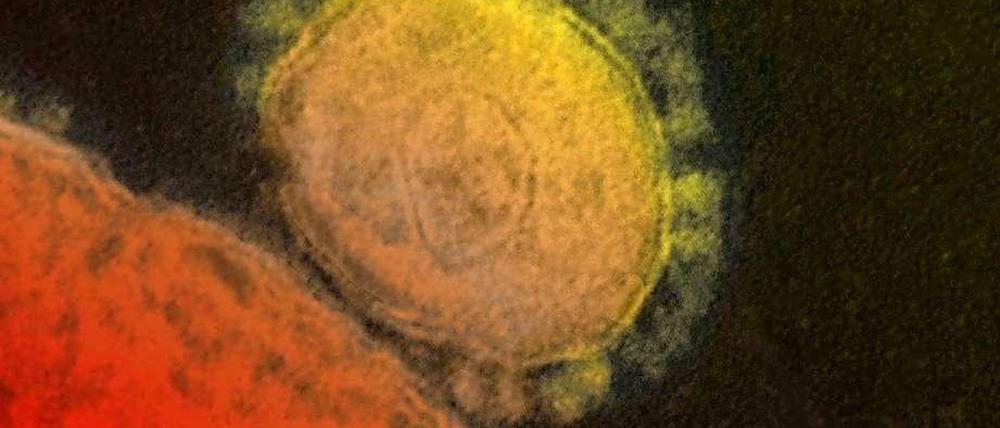

Gefährliches Virus: WHO: Mers ist noch kein Notfall

Die Zahl der Infektionen steigt weiter. Die Weltgesundheitsorganisation stuft die Lage dennoch nicht als "internationalen Notfall" ein. Sie fordert, mögliche Ansteckungswege besser zu erforschen.

Mers wird durch ein Virus ausgelöst, das unter anderem Zellen tief in der Lunge zerstören kann. Deshalb bekommen manche Menschen schwere Lungenentzündungen. Es gibt weder ein Medikament noch eine Impfung. Vor allem ist drei Jahre nach der Entdeckung der Seuche immer noch nicht klar, wie und wo sich die Menschen anstecken. Das müsse dringend aufgeklärt werden, sagte Fukuda und wiederholte damit eine alte Forderung. Er sei „hoffnungsvoll“, dass die Studien nun begonnen oder abgeschlossen werden. „Wenn Seuchen ausbrechen, hilft nur eines: Transparenz. Sonst riskiert man eine Panik.“ Pilger und Besucher von anderen Massenveranstaltungen sollten auf jeden Fall über das Mersvirus aufgeklärt werden.